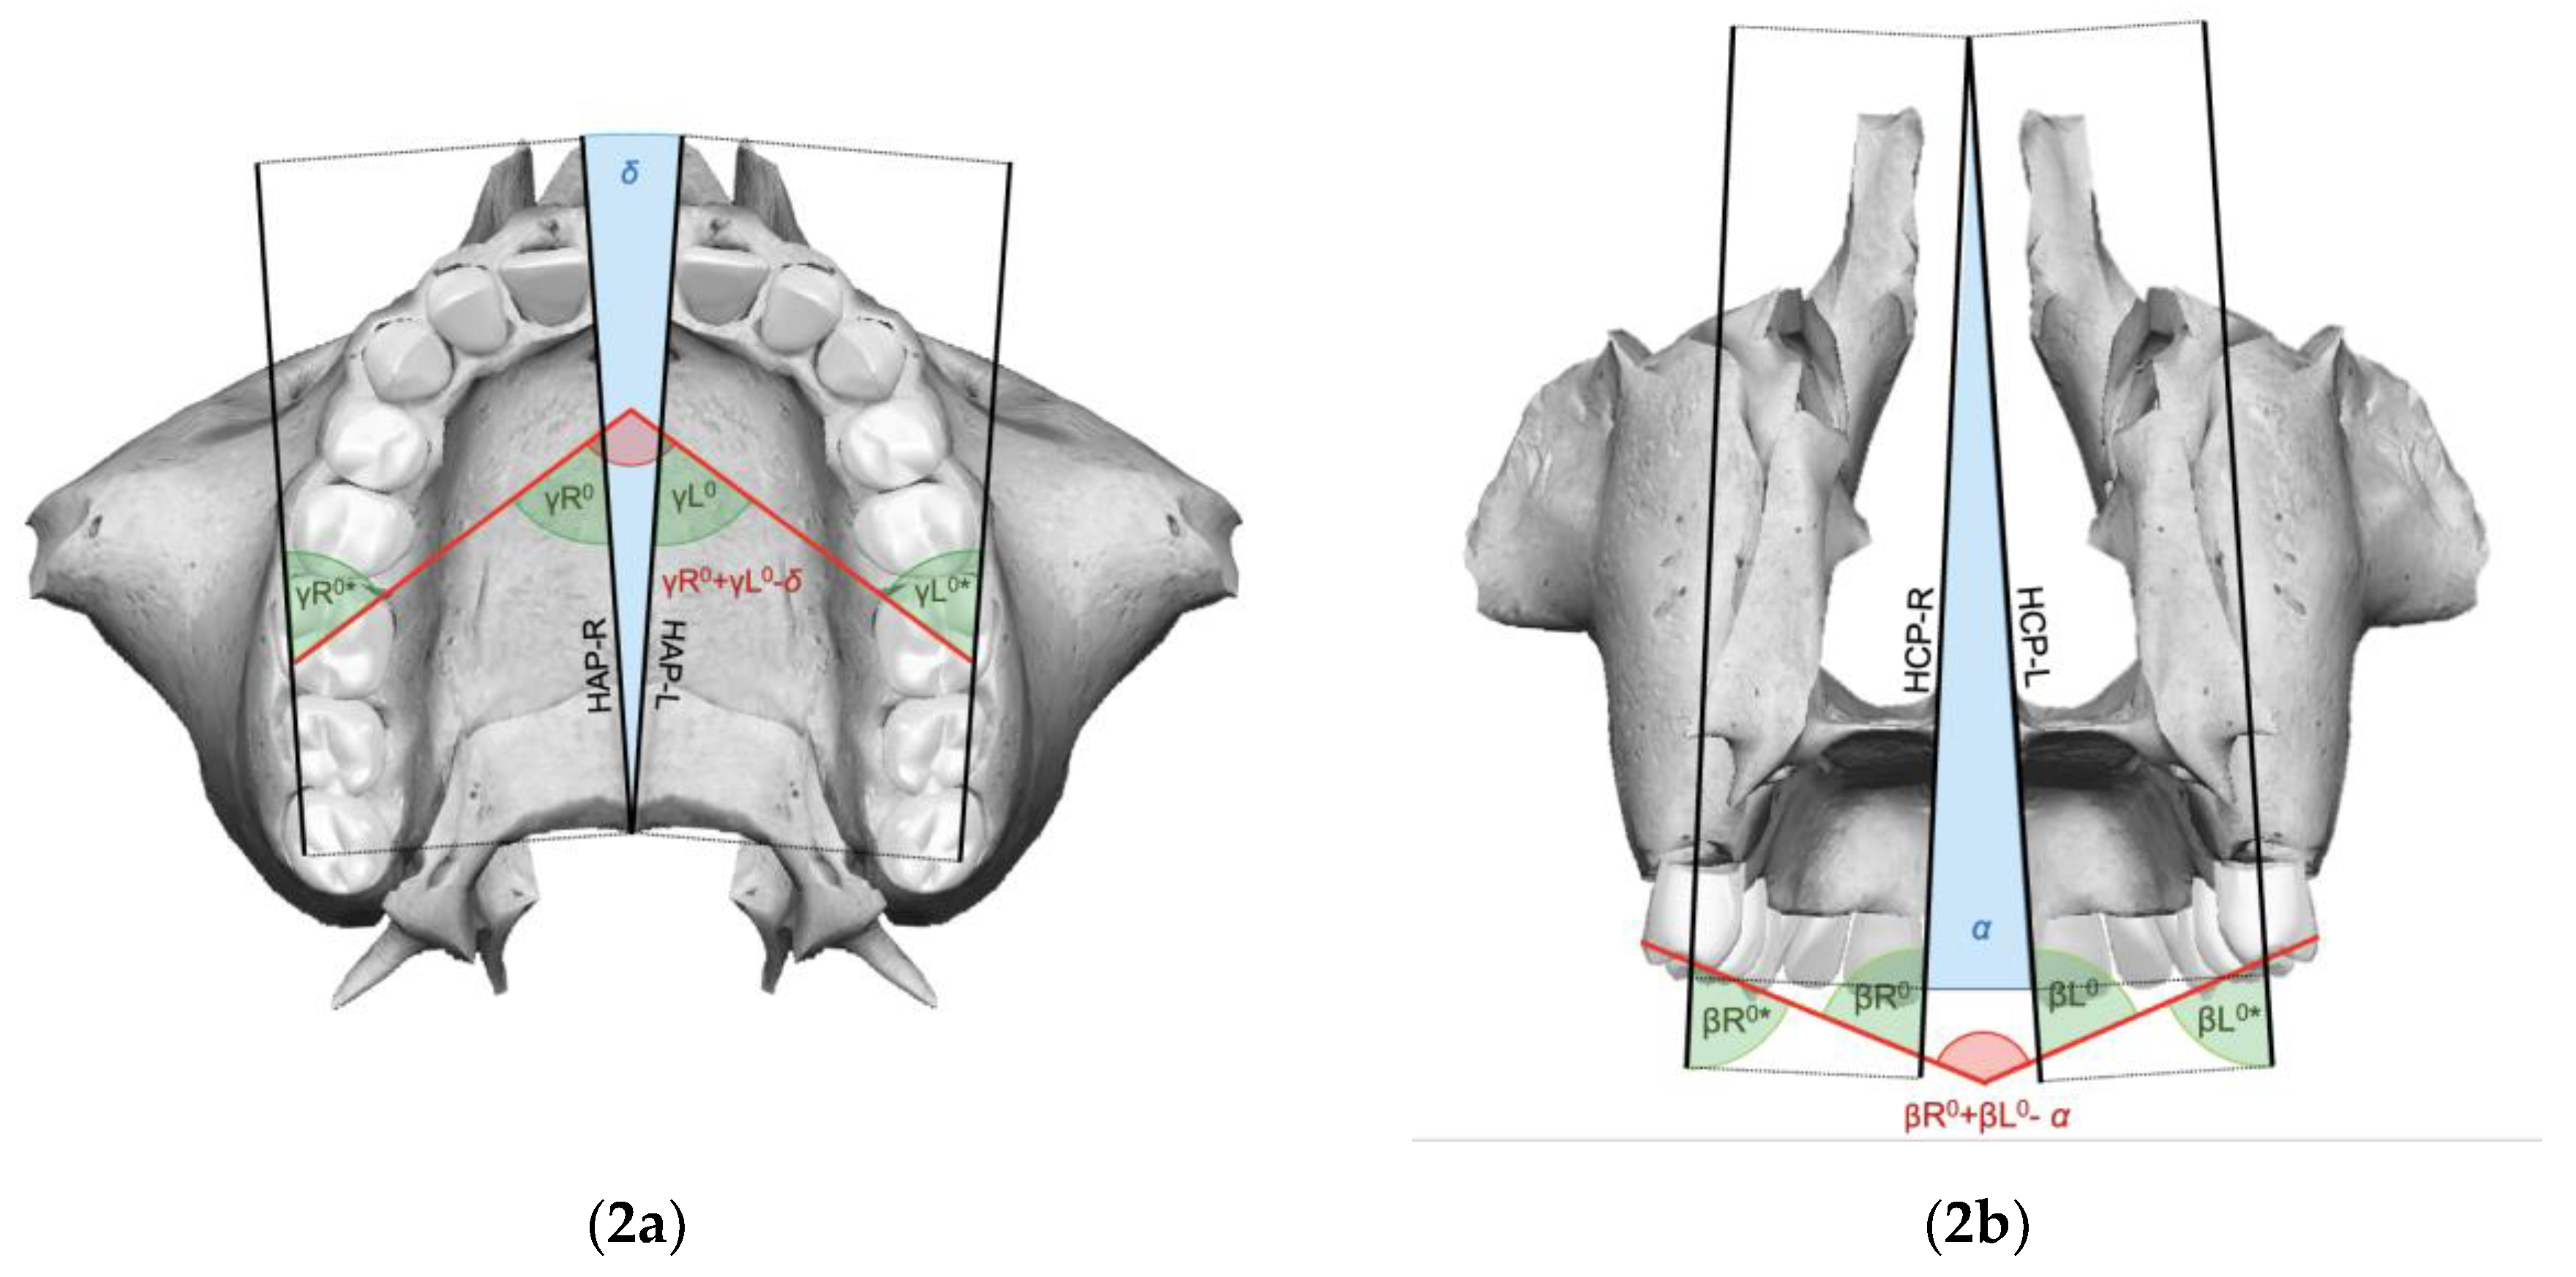

| Orthopedic expansion angle on frontal view (α) | Angle corresponding to the pyramid-like splaying pattern of the post-expansion maxillary components, projected on the frontal view |

| Orthopedic expansion angle on axial view (δ) | Angle corresponding to the pyramid-like splaying pattern of the post-expansion maxillary components, projected on the axial view |

- For clinical improvements to be achieved in the expansion phase, it is necessary that the molar rotation angle (γ) and the intermolar angle (β) at the end of expansion are less than the difference between the respective pre-treatment angle and the orthopedic expansion angle.

- It is possible to calculate expansion angles (α and δ) by a reliable and reproducible method, respecting radiation protection principles, without requiring post-expansion CBCT scans, with the following formulas: